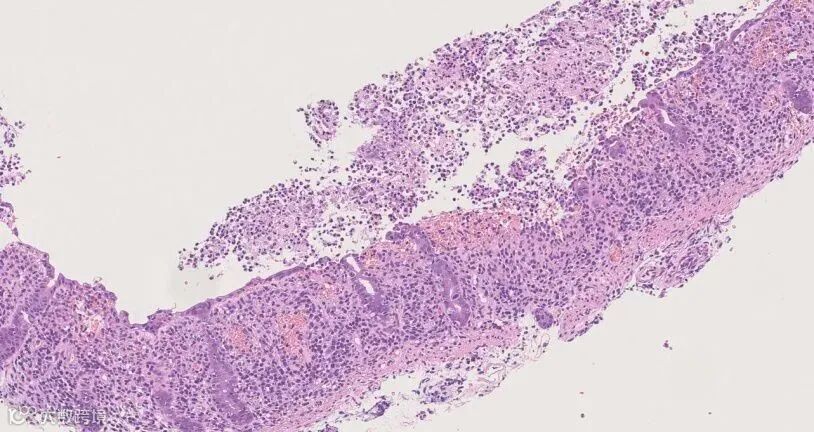

▲慢性炎症细胞浸润有癌变的风险